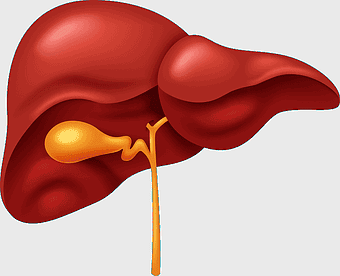

human liver anatomy, medical imaging liver, liver radiology scan, human digestive system liver, abdominal organ visualization, internal anatomy illustration, liver health diagram -

1000x1000px

liver illustration, human liver cartoon, cartoon liver image, liver organ diagram, liver anatomy visual, medical liver graphic, liver health depiction -

631x578px

human liver anatomy, liver disease symptoms, bile production process, liver function tests, digestive health illustration, organ detoxification, gastrointestinal health benefits -

1200x800px

liver with gallbladder diagram, human liver function, bile production organ illustration, digestive system anatomy, liver and bile duct visual, human anatomy medical graphic, hepatology reference image -

1000x1408px